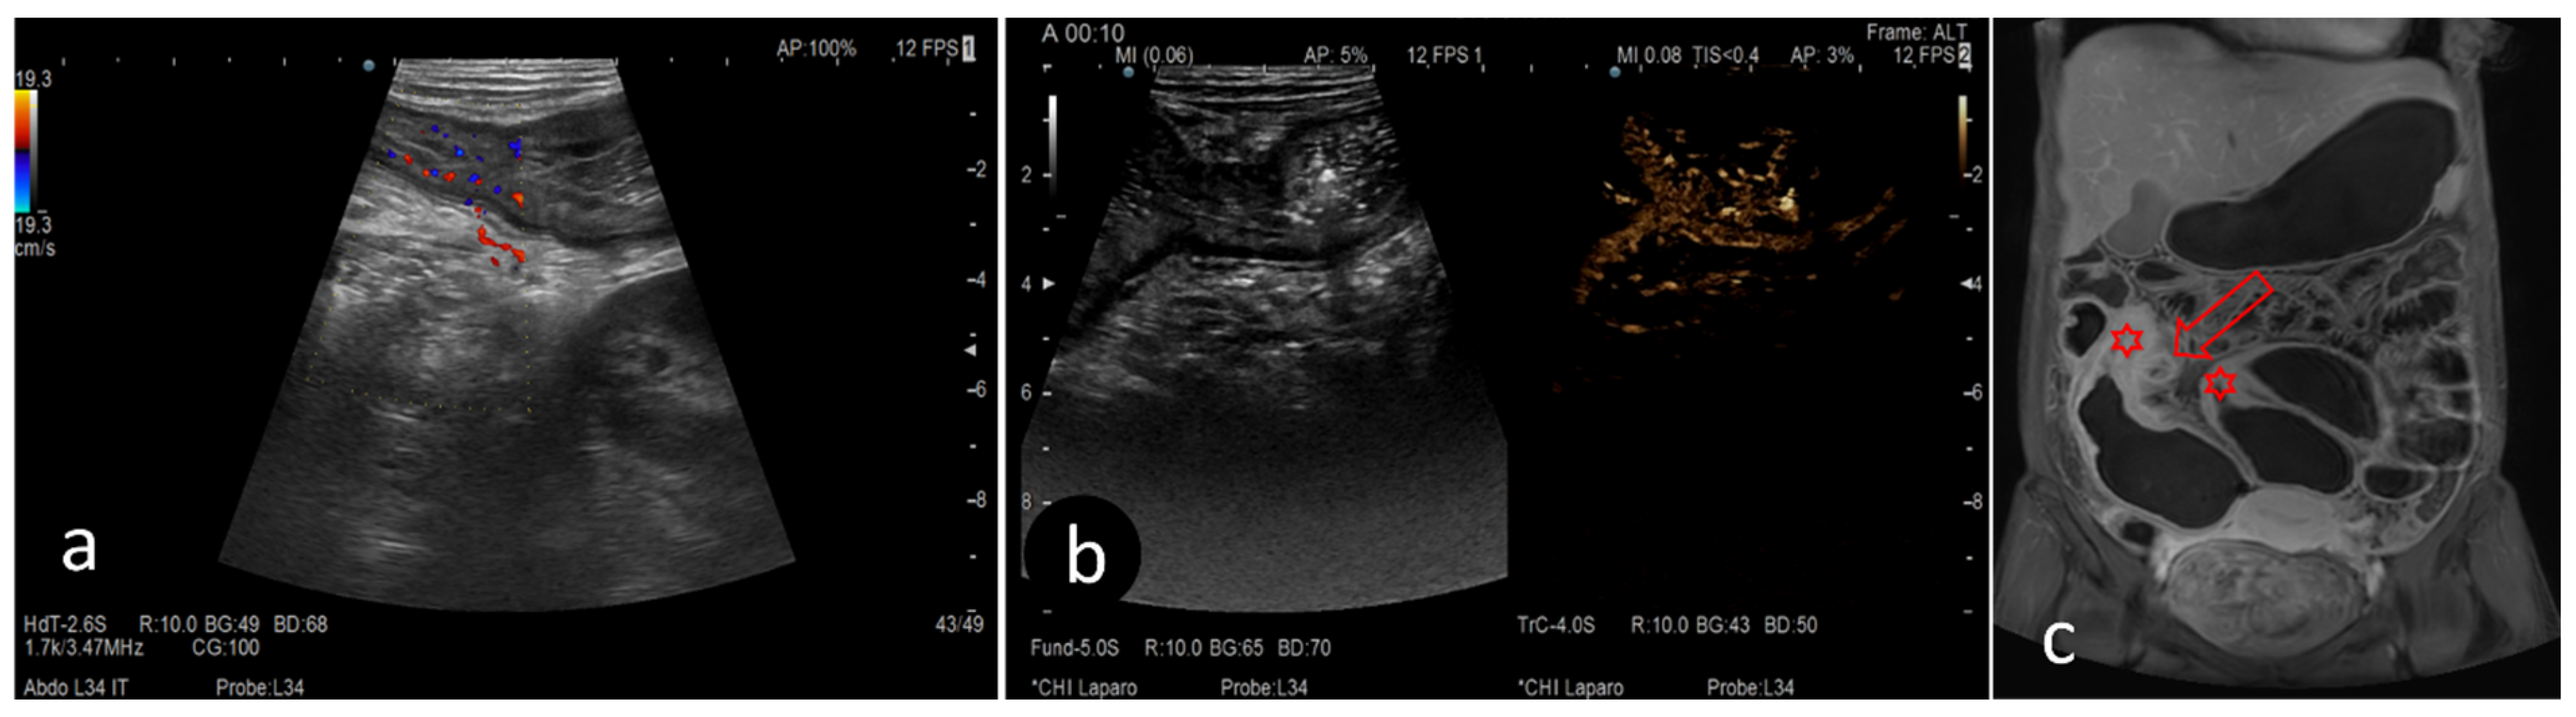

2.3. Ultrasound

2.4. Magnetic Resonance Enterography